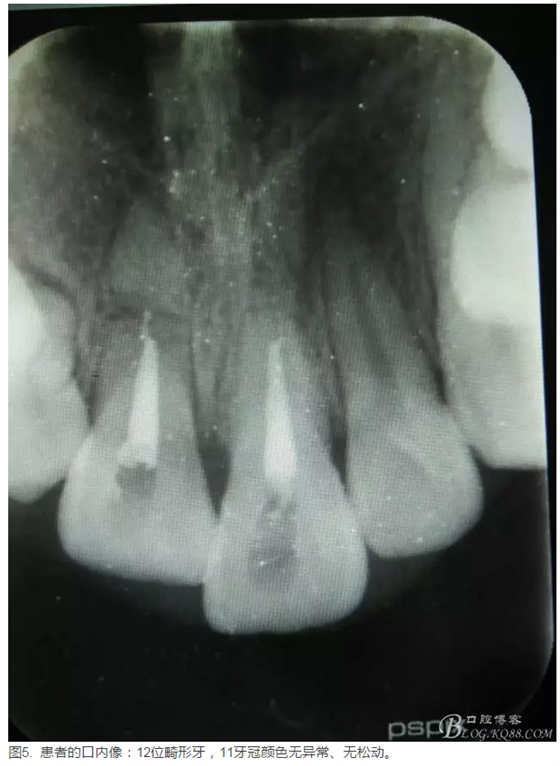

患者、李xx、男、15歲,主訴:牙不齊,矯正牙齒。??茩z查:發(fā)現(xiàn)11、21根尖三分之一折斷,患者否認(rèn)有外傷史。正畸科治療建議如圖1.。術(shù)前簽手術(shù)同意書。

圖1.患者術(shù)前的正畸科檢查病歷: